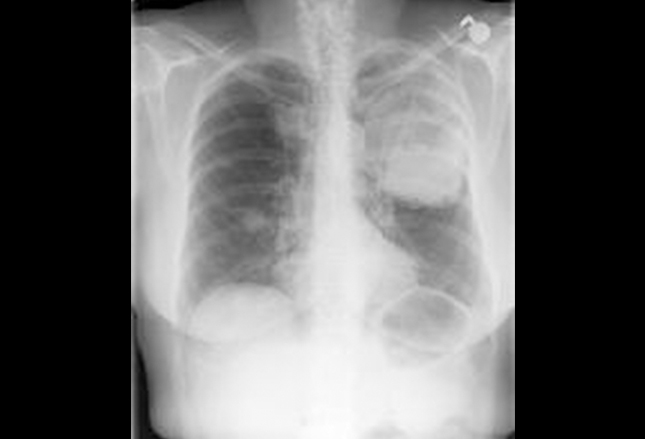

正面胸片显示左肺沉积扩张至左肺上叶,同时可见右肺中叶结节,以及广泛的气管周围淋巴结。